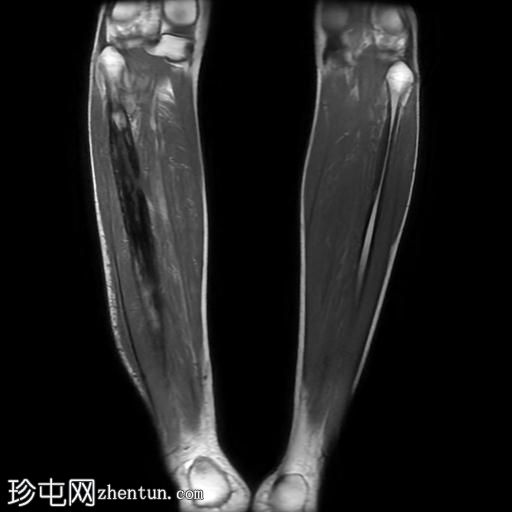

轴位

STIR序列

腓骨可见广泛的骨髓水肿,伴有明显的皮质和骨膜增厚,整个腓骨均呈高信号。腓骨外侧中下三分之一交界处可见局灶性皮质破坏,并可见一条高信号瘘管延伸至周围皮肤。

此外,软组织(包括肌肉和皮下组织)也受累。